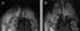

Angioplasty, also known as balloon angioplasty and percutaneous transluminal angioplasty (PTA), is a minimally invasive endovascular procedure used to widen narrowed or obstructed arteries or veins, typically to treat arterial atherosclerosis. A deflated balloon attached to a catheter (a balloon catheter) is passed over a guide-wire into the narrowed vessel and then inflated to a fixed size. [Source: Wikipedia ]